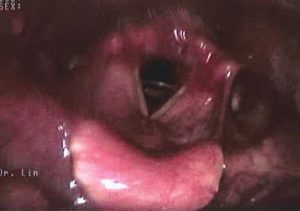

Figure 1. Larynx affected by reflux

Figure 3. Larynx affected by severe reflux